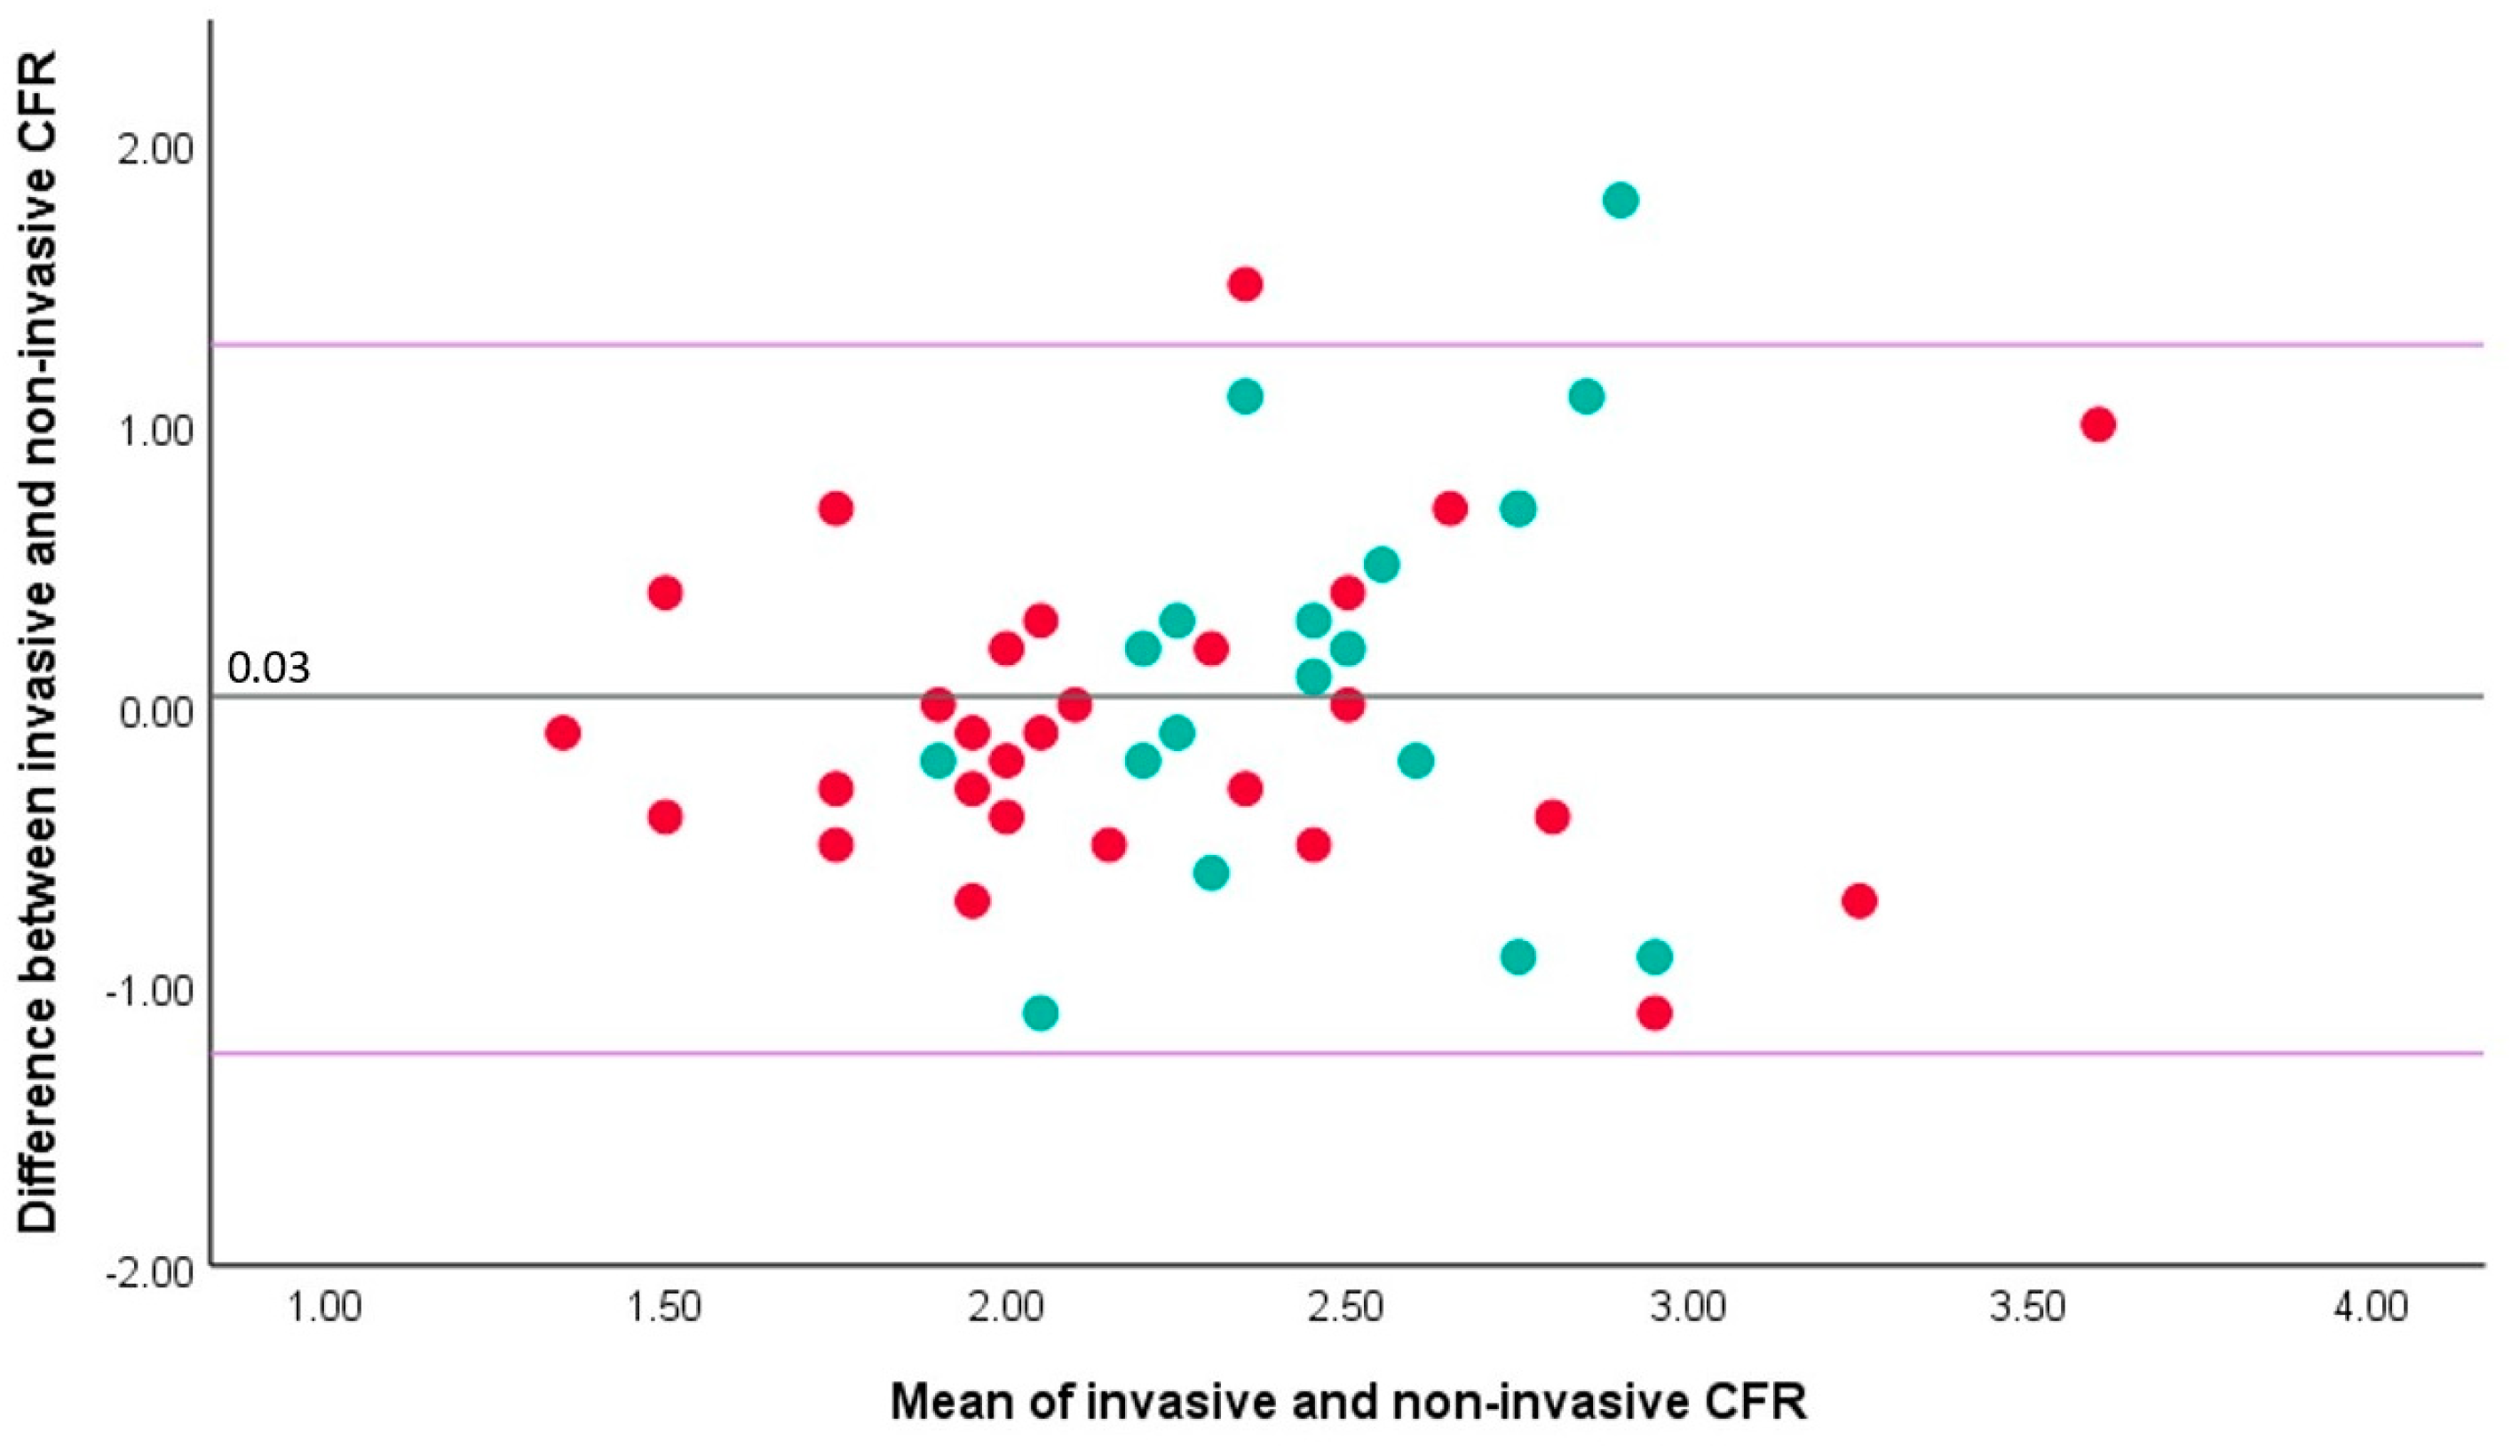

3.2. Correlation between Invasive and Non-Invasive CFR

4.1. Correlation between Intracoronary- and Echocardiography-Derived CFR